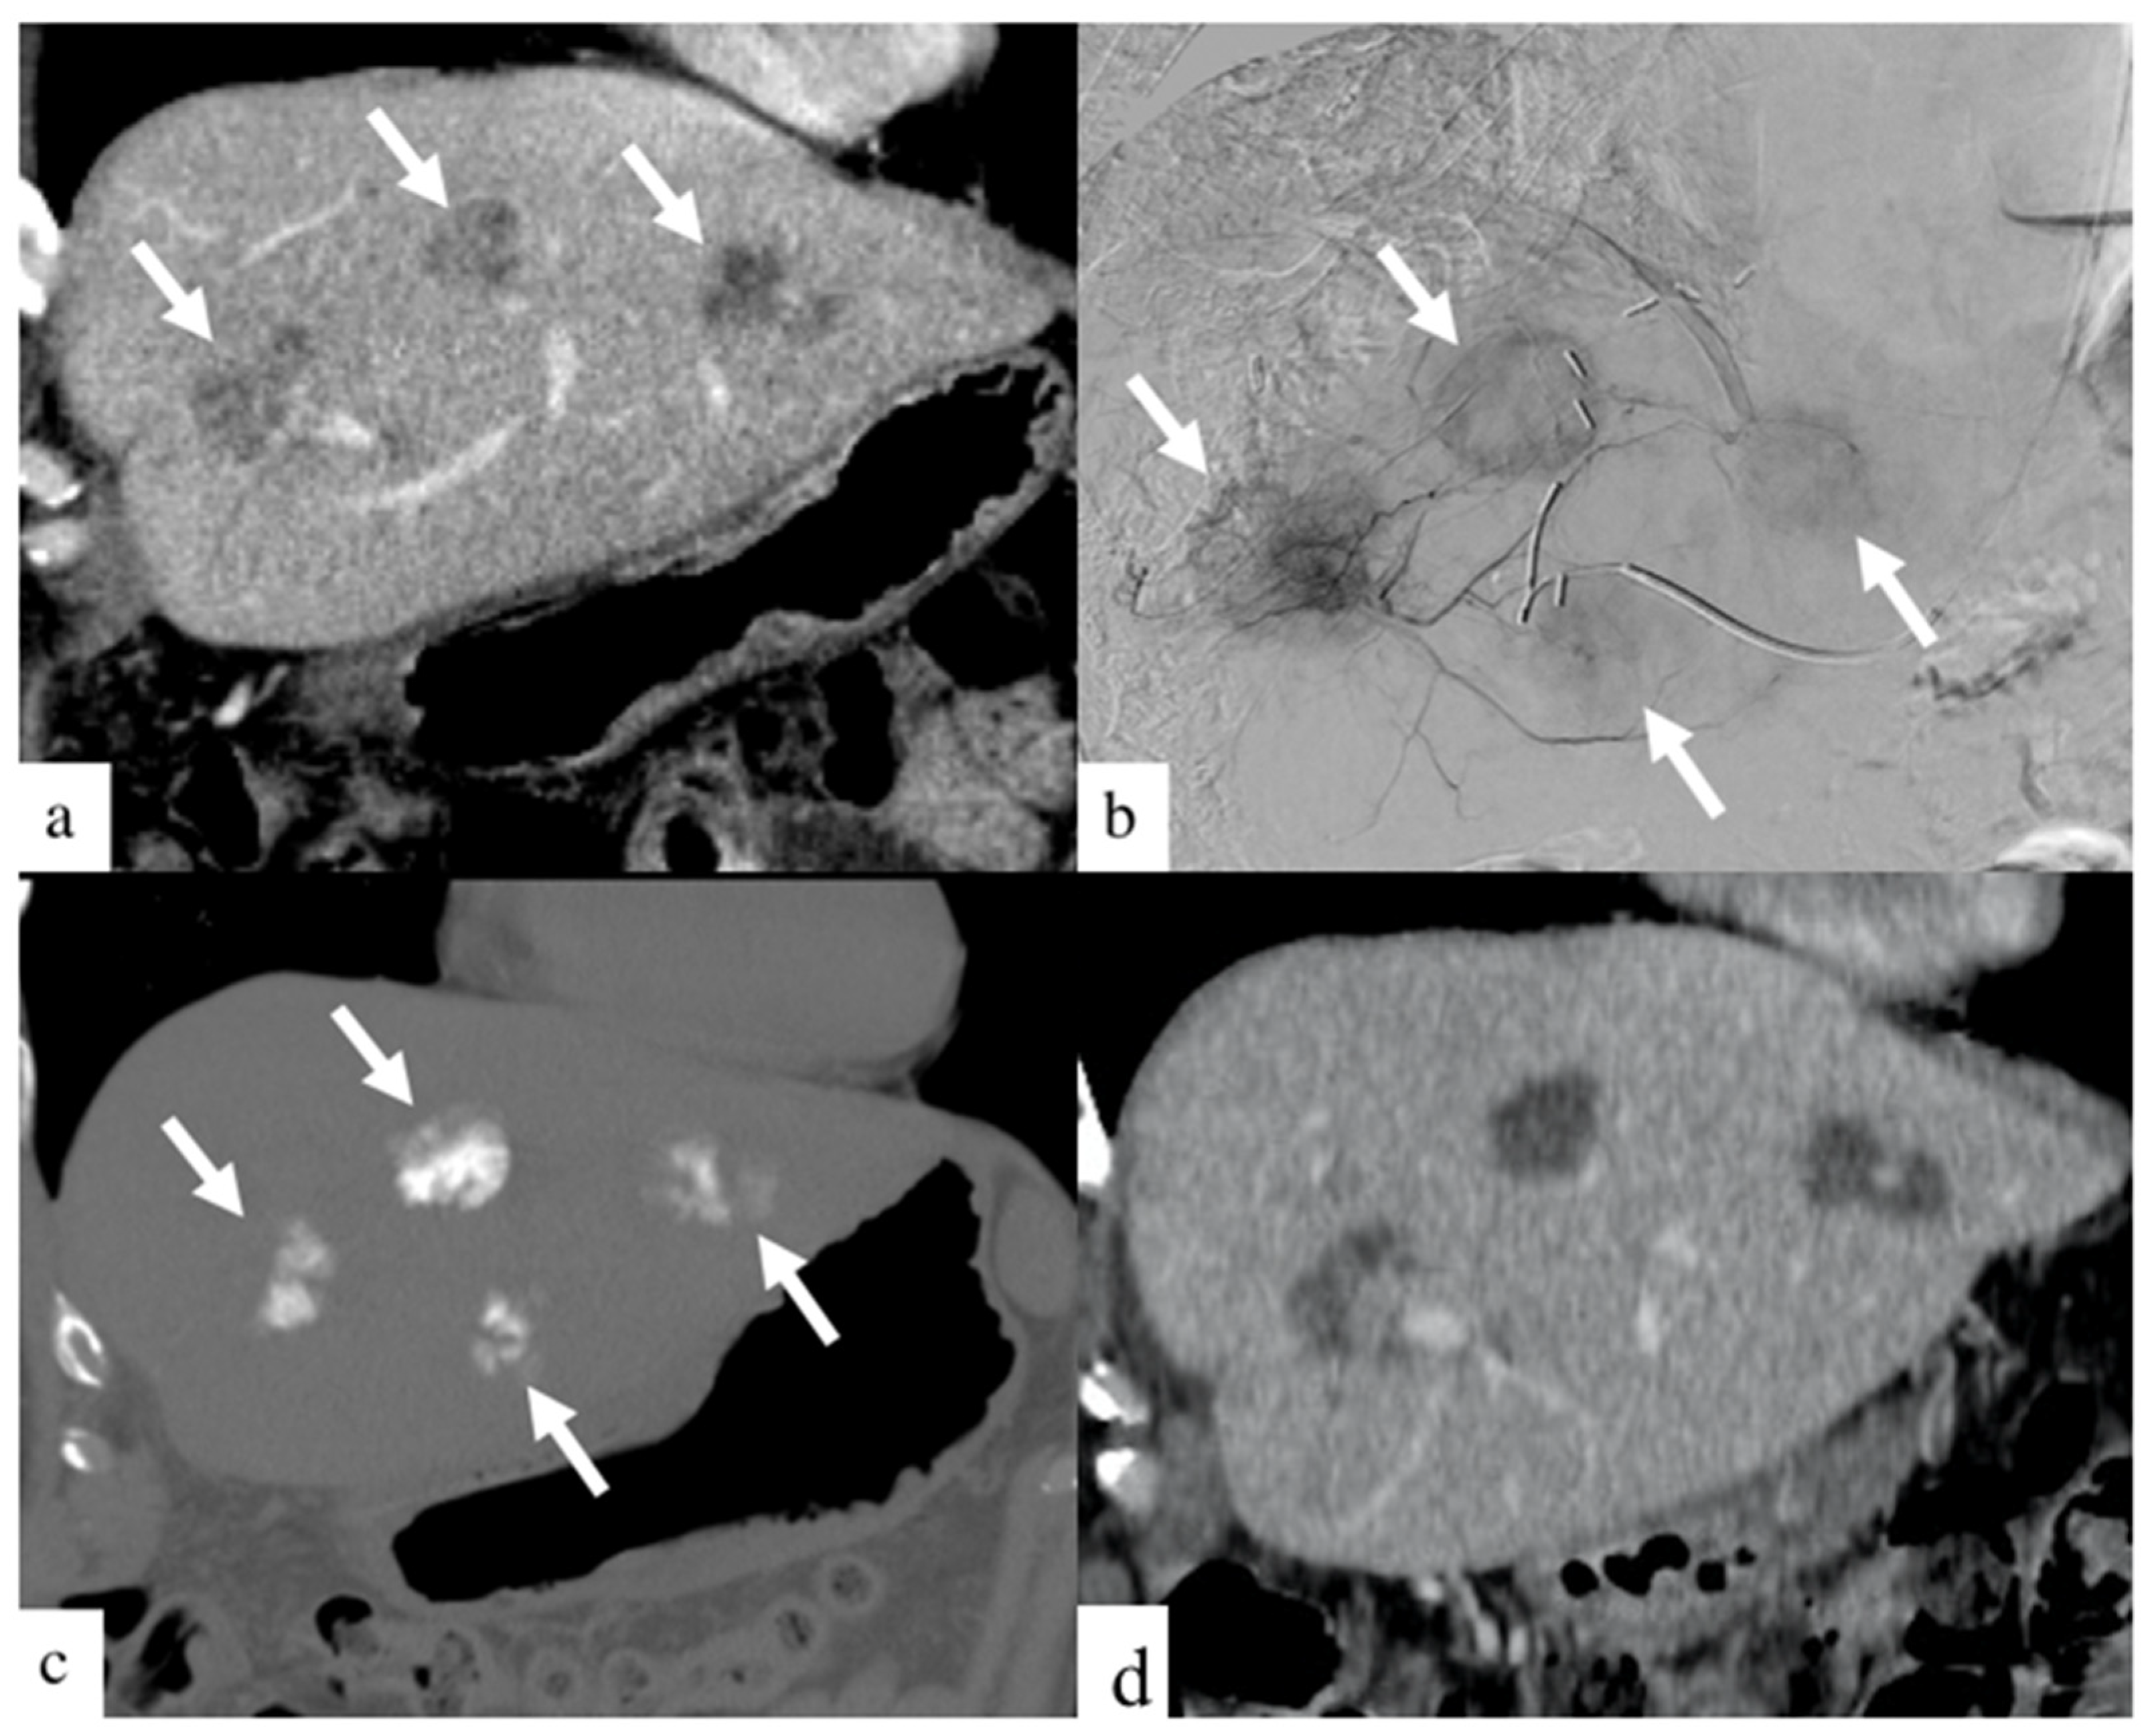

DEBIRI therapy is known to be safe in patients receiving concurrent systemic chemotherapy [18]. Although prior randomized controlled trials [12,13] and prospective studies [19,20] have shown the safety of treatment with larger beads, few studies have reported the safety profile of smaller beads [14,16]. Smaller bead size has the potential of delivering higher drug concentrations distally into the tumor bed, as depicted in Figure 2 and Figure 3. This retrospective study is, to our knowledge, the largest study evaluating the safety and efficacy of 40 and 75 µm calibrated drug-eluting beads in the treatment of metastatic CRC.

Figure 3.

Images of a patient with history of colorectal cancer who underwent a single small particle DEBIRI TACE session of the left lobe. Portal venous phase coronal CT image obtained pre- treatment (a) shows three of the four metastases in the left lobe (arrows). Digital subtraction angiographic images obtained through microcatheter (b) shows hypervascularity of all four metastases (arrows). Non-enhanced coronal CT image obtained 1 h post-treatment (c) shows intra-tumoral staining of iodinated contrast (arrows). Coronal CT image (d) of a patient one- month post-DEBIRI treatment.